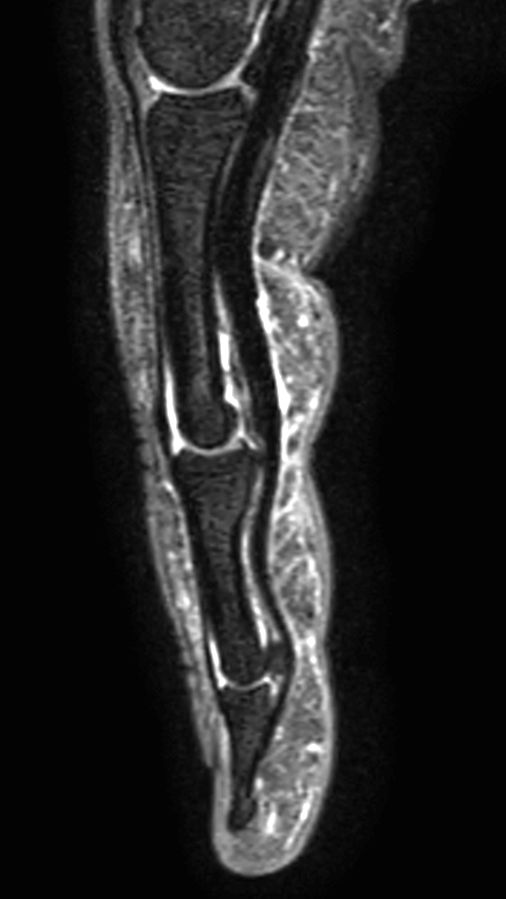

Sagittal T2w TSE mDIXON XD